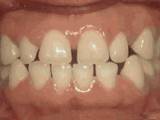

症状表现:疾病外因等造成的牙列稀疏,牙槽骨过长或牙齿缺失,导致排列太宽松,零零散散。

症状表现:下牙边沿覆盖上牙超过1/3,俗话说的地包天。

下一篇:牙结石介绍